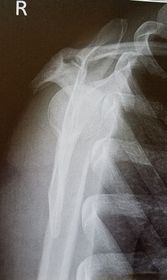

| AP Humerus | humeral epicodyles not in profile radial head, neck and tuberosity to not superimpose ulna arm is externally rotated (greater tubercle in profile) |

| Lateral Humerus | over rotation places the humeral head within the field of the chest |

| Lateral Humerus | epicondyles are not perpendicular humerus is internally rotated (lesser tubercle is in profile medially) overrotation |

| AP Humerus | ANATOMY: entire humerus: shoulder -> elbow CRITERIA: greater tubercle in profile - hand externally rotated humeral epicondyles are parallel to IR POSITIONING: CR perpendicular @ midhumerus |

| Lateral Humerus | ANATOMY: entire humerus: shoulder -> elbow CRITERIA: lesser tubercle in profile - arm internally rotated epicondyles superimposed POSITIONING: pt rotated 15-20 degrees from PA to get arm lateral and away from chest - flex elbow 90 degrees CR perpendicular @ midhumerus |